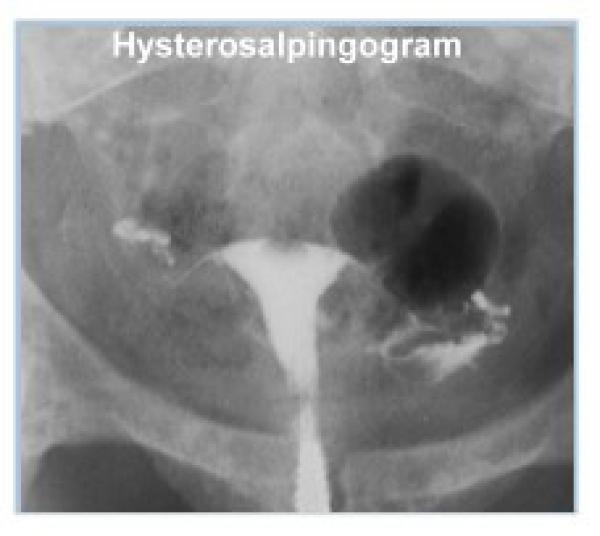

Семь пациенток со вторичной аменореей были диагностированы как тяжелые маточные синехии с помощью гистеросальпингографии (ГСГ) и гистероскопии, которые выявили короткие, узкие и/или рубцовые полости матки в форме конуса или столбца.